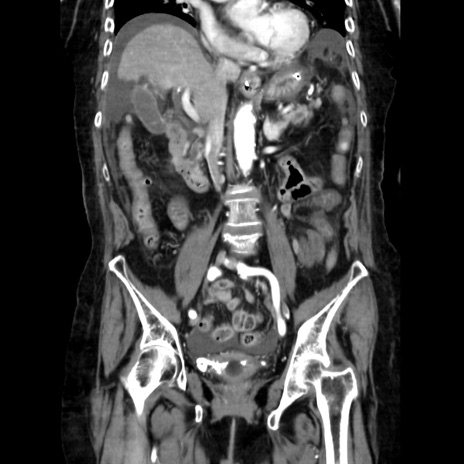

症例40(冠状断像)

【症例】90歳代女性

【主訴】腹痛・嘔吐

【現病歴】 食欲低下、嘔吐があり昨日他院受診。肺炎と診断され入院となる。入院後より腹部全体に圧痛あり。胃管留置され経過みていたが、症状持続するため、

当院転院となる。

【身体所見】腹部:中央に激痛あり、圧痛あり、反跳痛不明

【データ】WBC 17100、CRP 18.82

冠状断像